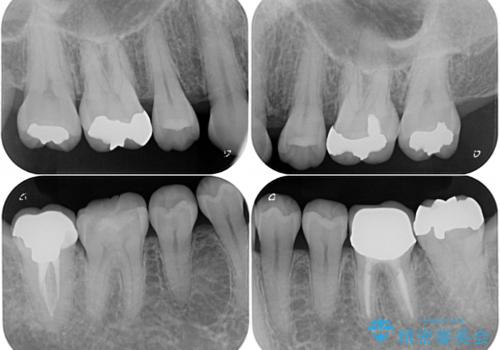

- 以前行った抜歯矯正が後戻りし、開いてしまったスペースが気になるとのことで来院された患者様です。

矯正治療後には気になっていた銀歯をセラミッククラウンやセラミックインレーにて治療することとしました。

上顎前歯を左右対称となるように歯列を整えたいとのことでしたが、すり減って形態が大きく異なっていたため、できる範囲での仕上がりとなりました。